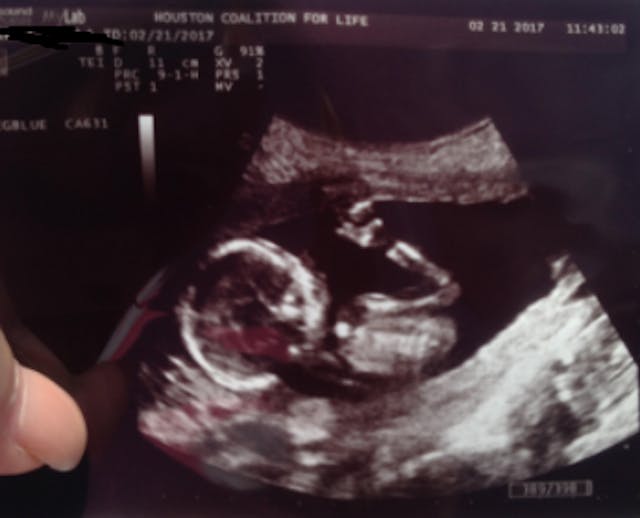

The ultrasound, which you can see below, showed only a round blob.

I asked if I could see her ultrasound and she handed it to me. As a medical professional, I knew exactly what I was looking at when I saw it. I asked her how far along she was and she said 16 weeks (it was on the bottom of the ultrasound, but I wanted to hear if the clinic had told her).

At 16 weeks, Amara’s baby was fully formed, with arms, legs, fingers and toes. According to the Endowment for Human Development, a baby at 16 weeks has “a highly complex brain”, is already left or right-handed, breathes amniotic fluid, and has fingerprints that are unique and different from those of any other human being who has ever lived. He or she responds to touch and pressure and can suck his or her thumb. Yet the ultrasound only showed a round circle.

An untrained eye, looking at her ultrasound, would have only seen a blob of tissue. No one had shown this woman her baby. They simply showed her the cranium. Why would Planned Parenthood take an ultrasound image of the diameter of the cranium (the head)?

Because this is the largest part of the baby’s anatomy that needs to fit through the canulla and it is this measurement that determines what size canulla is used.

The ultrasound was showing a picture of the baby’s head, taken from above. All it showed was the round head. Even though the child at this stage had arms, legs, fingers and toes, Planned Parenthood led Amara to believe that her baby was only a blob, by showing her an ultrasound taken at a deceptive angle.